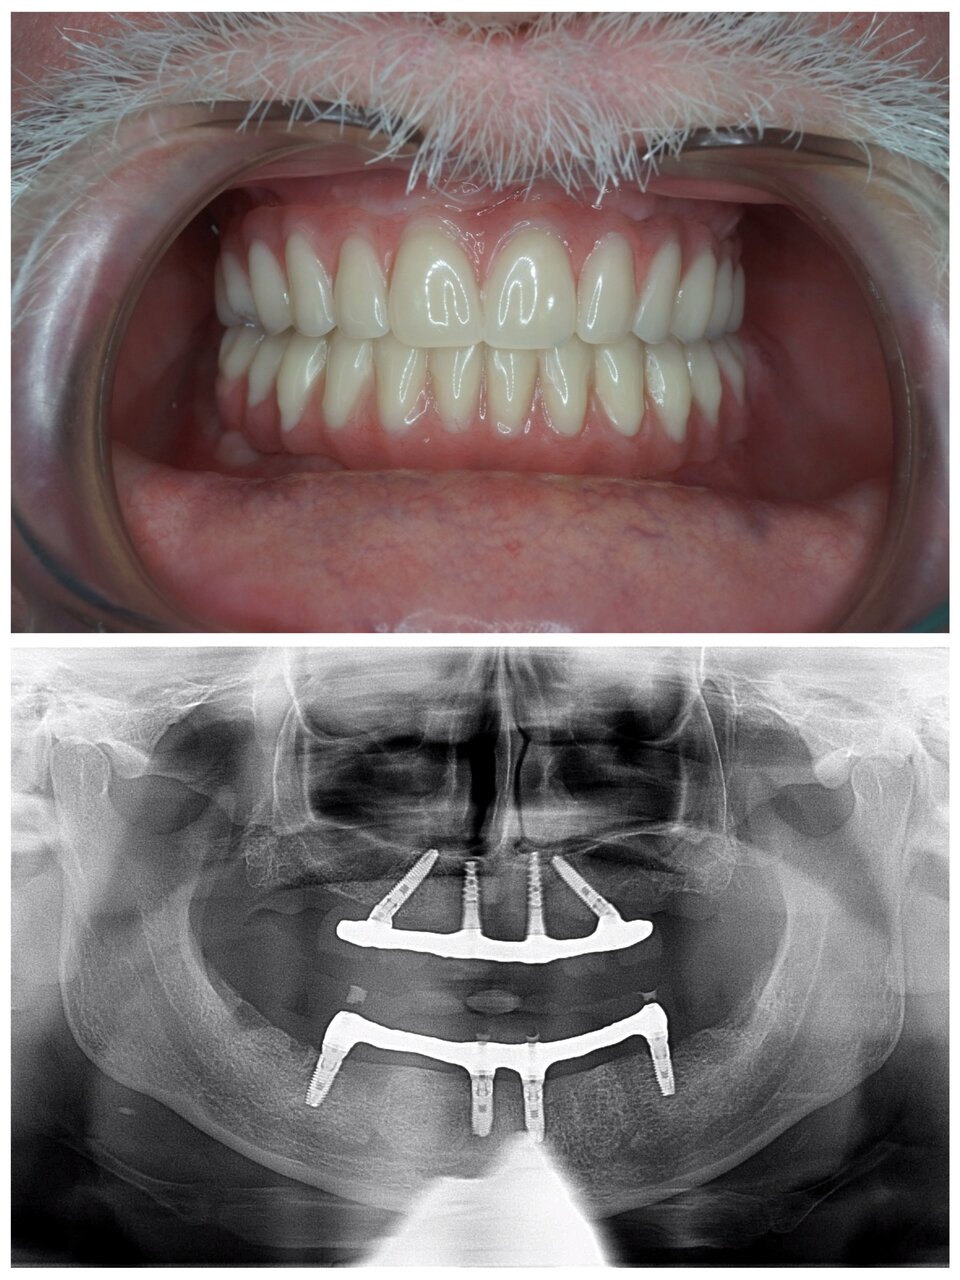

В клинике работают квалифицированные специалисты, включая стоматологов, ортодонтов, ортопедов и имплантологов. Основные направления деятельности включают терапию, хирургию, эстетическую стоматологию, протезирование, имплантацию, ортодонтическое лечение и гигиену полости рта. Среди дополнительных услуг доступны рентгенография, компьютерная томография, лечение под микроскопом, костная пластика, а также современные методы цифровой стоматологии CAD/CAM.

- протезирование

- коронки

- Положительные отзывы о протезировании (коронки, мосты, импланты).